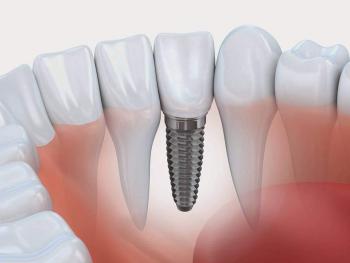

O implante dentário consiste na instalação cirurgica de uma raiz artificial de um dente.

O implante tem o formato de um pequeno parafuso e é feito em Titânio que é um material biocompativel.

Ele será rosqueado no osso no local do dente perdido, e servirá de apoio a uma coroa ou prótese dentária.